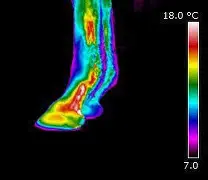

Die Thermographie ist ein bildgebendes Verfahren, das Temperaturmuster auf der Körperoberfläche sichtbar macht. Diese Temperaturveränderungen entstehen durch entzündliche Prozesse, Gewebereizungen, Belastungsreaktionen oder andere Anomalien, die sich in der Thermografie als deutliche Erwärmungen oder Abkühlungen darstellen.

Thermografische Muster können aus oberflächlichen und tieferliegenden Strukturen stammen – einschließlich Bereichen, die mit Knochen, Knochenhaut, Gelenken, Sehnenansätzen, Bändern und Gefäßen in Zusammenhang stehen.

Hufe und Hufkapsel (inkl. Bereiche über dem Hufbein)

Gelenke (Fessel-, Karpal-, Sprung-, Kniegelenk usw.)

Sehnen- und Bandbereiche

Bereiche über Knochenstrukturen (z. B. Röhrbein, Fesselbein, Wirbelsäule)

Von jeder Region werden Bilder aus mehreren Perspektiven aufgenommen (links, rechts, vorne, hinten). So entsteht eine umfassende thermografische Dokumentation, in der alle relevanten Strukturen – inklusive knochenbezogener Bereiche – sichtbar werden.